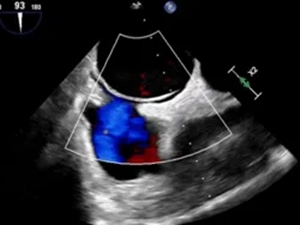

经食道超声

卵圆孔未闭